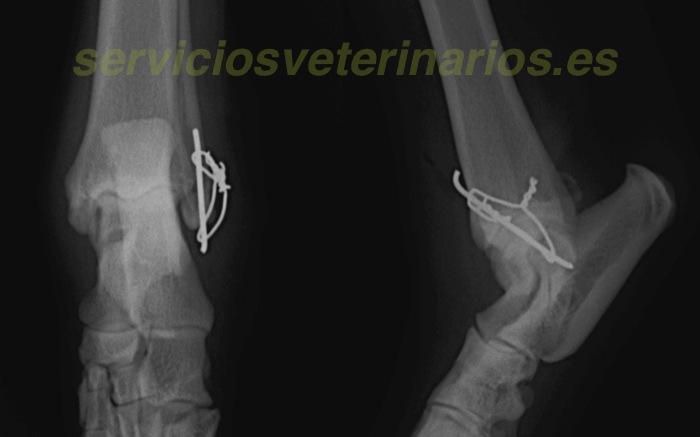

| Tratamiento | Tras comprobar que el motivo de la inestabilidad está en una fractura ósea sobre el extremo del maleolo, punto de inserción ligamentoso, se cambia el procedimiento inicial para lesión ligamentosa (tres tornillos y ligamentos artificiales de poliéster ) a un procedimiento para esta fractura con aguja y banda de tensión. |

Se prepara una banda de tensión con las alas para ser rotadas fácilmente. El alambre así tensionado ejercerá la misma fuerza en ambos lados. Una vez ajustada la fuerza, con cuidado para no fracturar el pequeño fragmento distal, se cortan y rotan internamente los extremos.

Se deja con férula durante 3 semanas para evitar tensiones excesivas de manera prematura ya que el peso cercano a 30 kg puede ejercer demasiada fuerza para el pequeño fragmento distal. El apoyo es correcto al retirar la férula así como las radiografías y exploraciones. Aun así se limita la actividad un mes mas.